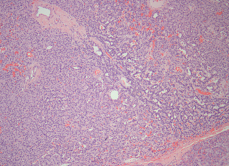

Figure 5a HE 10x: Low –power photomicrograph demostrating a neuroendocrine tumor. The tumor shows solid, ribbonlike, and acinar growth patterns.

Figure 5b HE 40x: Higher magnification showing monomorphous cell, large nuclei and small nucleoli as well as inconspicuous cytoplasma and fine cromatina. Mitoses are rare.

Figure 5c Low antibody staining against Ki-67 (nuclear protein present during all active phases of cell cycle and absent from resting cells).

Figure 5d Intense staining against synaptophysin (citoplasmatic protein located in neurons and neuroendocrine tumors).